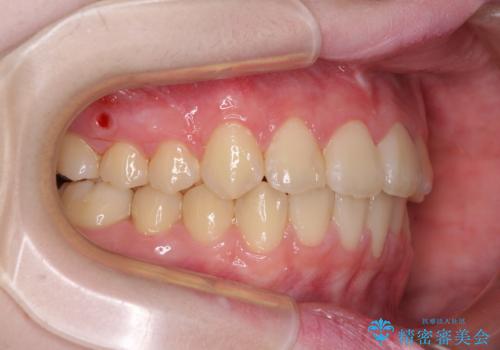

治療途中で大学受験があり、来院できない時期がありましたが、2年以内で満足のいく歯並びを達成することができました。

- 1年10ヶ月